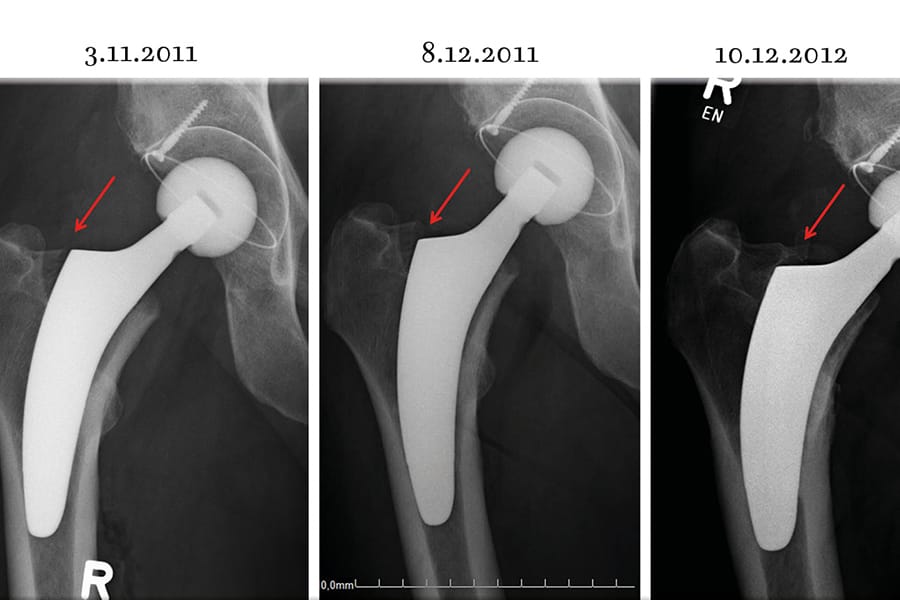

The clinical articles address diverse subspecialties. Trapeziometacarpal joint imaging in the surgical management of basal thumb arthritis informs operative planning in hand surgery, while orthopaedic surgical site infection prevalence in Egypt contributes epidemiological data on infection control. Ligamentous reconstruction is examined through revision ACL reconstruction, and implant selection is explored in the context of short stems for obese patients. The issue concludes with an anatomical and fluoroscopic review of percutaneous screw fixation of the pelvic ring and acetabulum.